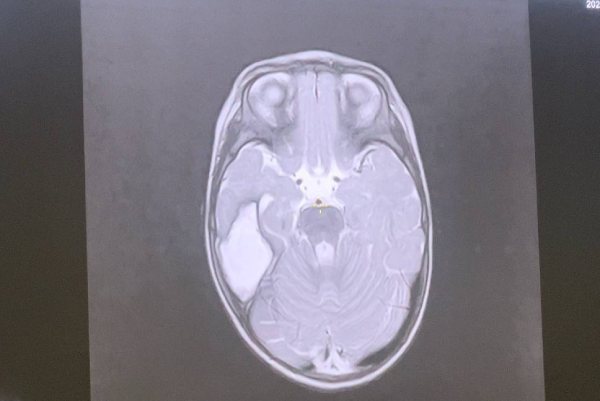

В Иркутске прооперировали младенца с опухолью головного мозга

Нейрохирурги Иркутской областной детской клинической больницы прооперировали младенца с объёмной опухолью головного мозга. За год жизни малышка перенесла 50 приступов эпилепсии.

Годовалую девочку с рождения беспокоили приступы эпилепсии – всего их было не менее 50. Причиной стала опухоль в правой височной области размером 3 на 4 сантиметра. Эпилепсия грозила жизни пациентки и могла повлечь за собой когнитивные нарушения.

- Требовалось удаление опухоли. Операция выполнялась с помощью микроскопа, технологии интраоперационного УЗИ и нейронавигации – по передовым методикам визуализации и наведения, которые помогают точно определять и достигать целевых областей в головном мозге. Это позволило минимизировать длительность вмешательства и наркоза для пациентки, - рассказал главный врач больницы, известный хирург Юрий Козлов.

Всё прошло успешно. Девочка находится под наблюдением заведующего отделением нейрохирургии Артёма Журкина. Он отмечает, что приступы эпилепсии её больше не беспокоят. Неврологического дефицита нет.